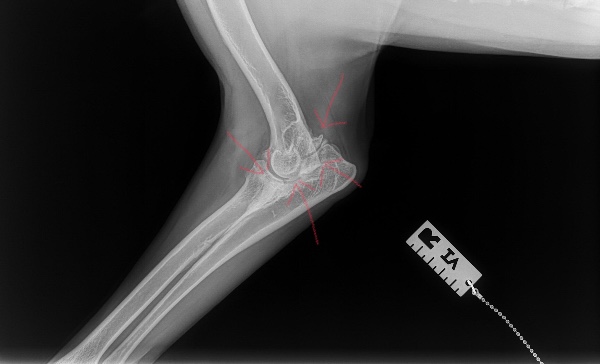

When Koda was five months old she was diagnosed with Genetic Elbow Dysplasia, and more recently Severe Advaced Osteoarthritis. Up until this point, we have managed her symptoms with diet, supplements, stretching, massage, swimming , and staying cautiously and consistently active with moderate hiking, walking and adventuring. In September she had an incident that acutely exacerbated her condition, and her pain got significantly worse. Some days, she tries to not use her effected leg at all, she can no longer hike, walk without extreme pain, run, jump, or play with any of her dog friends. She is only 1 and a half but is displaying the lameness and immobility you'd expect to see in an 11 year old dog.

When her pain got acutely worse in September we cut her exercise down to almost nothing, and transitioned her activity to swimming only, but her pain continued. We then started her on Adequan injections coupled with NSAIDs and a wider variety of supplements. When 5 weeks passed and we saw little to no improvement in her pain we were urged by our vet to seek the opinion of a Canine Orthopedic Specialist in Reno NV.

After meeting with him, and doing more diagnostic testing today he told us that because her Dysplasia and Osteoarthritis is so severe, at some point Koda will likely need to have her leg amputated in order to live a relatively pain free life. However, as a first step he strongly suggests an elbow surgery in hopes to buy her more time on four legs.

When Koda was five months old she was diagnosed with Genetic Elbow Dysplasia, and more recently Severe Advaced Osteoarthritis. Up until this point, we have managed her symptoms with diet, supplements, stretching, massage, swimming , and staying cautiously and consistently active with moderate hiking, walking and adventuring. In September she had an incident that acutely exacerbated her condition, and her pain got significantly worse. Some days, she tries to not use her effected leg at all, she can no longer hike, walk without extreme pain, run, jump, or play with any of her dog friends. She is only 1 and a half but is displaying the lameness and immobility you'd expect to see in an 11 year old dog.

When her pain got acutely worse in September we cut her exercise down to almost nothing, and transitioned her activity to swimming only, but her pain continued. We then started her on Adequan injections coupled with NSAIDs and a wider variety of supplements. When 5 weeks passed and we saw little to no improvement in her pain we were urged by our vet to seek the opinion of a Canine Orthopedic Specialist in Reno NV.

After meeting with him, and doing more diagnostic testing today he told us that because her Dysplasia and Osteoarthritis is so severe, at some point Koda will likely need to have her leg amputated in order to live a relatively pain free life. However, as a first step he strongly suggests an elbow surgery in hopes to buy her more time on four legs.